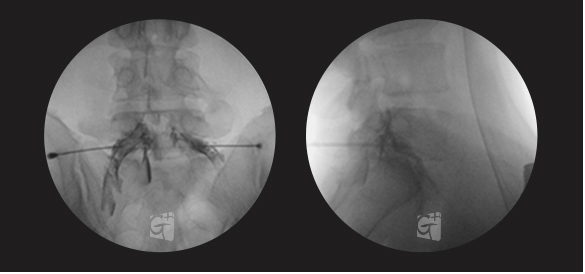

요추 신경성형술

꼬리뼈 구멍으로 카테타 삽입

척추관 안쪽으로 진입 약물 주입

원인부위 염증 제거 및 유착 박리

유착박리로 추간공 확보, 신경 압박 감소

척추관에서 약물이 잘 퍼져나오는 모습

허리 신경 전체를 효과적으로 치료